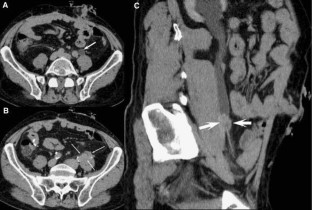

The combination of EU + CT correctly diagnosed 38 out of the 39 cases with a sensitivity of 97%. Correct diagnosis was established in all malignant cases (n = 17) but one benign case consistent with blood clots in the upper urinary tract was incorrectly diagnosed as a multicentric urothelial carcinoma. Sensitivity, specificity, and accuracy for the diagnosis of the underlying cause with EU + CT was 100%, 95%, and 97%, respectively. The final diagnoses were: urothelial carcinoma (n = 10), stone disease (n = 10), bladder tumor (n = 4), benign post-treatment ureteral stenosis (n = 4), ureteral invasion (n = 3), benign bladder disease (n = 2), urinary tract infections (n = 2), crossing vessels (n = 1), ureteropelvic junction obstruction (n = 1), retrocaval ureter (n = 1), and blood clots in the upper urinary tract due to bleeding renal metastasis from lung cancer (n = 1).

Combined EU and CT study allowed correct diagnosis of the underlying cause of delayed excretion or upper urinary tract dilatation in 97% of cases. The combination of EU and CT provides diagnosis reducing time and radiation.